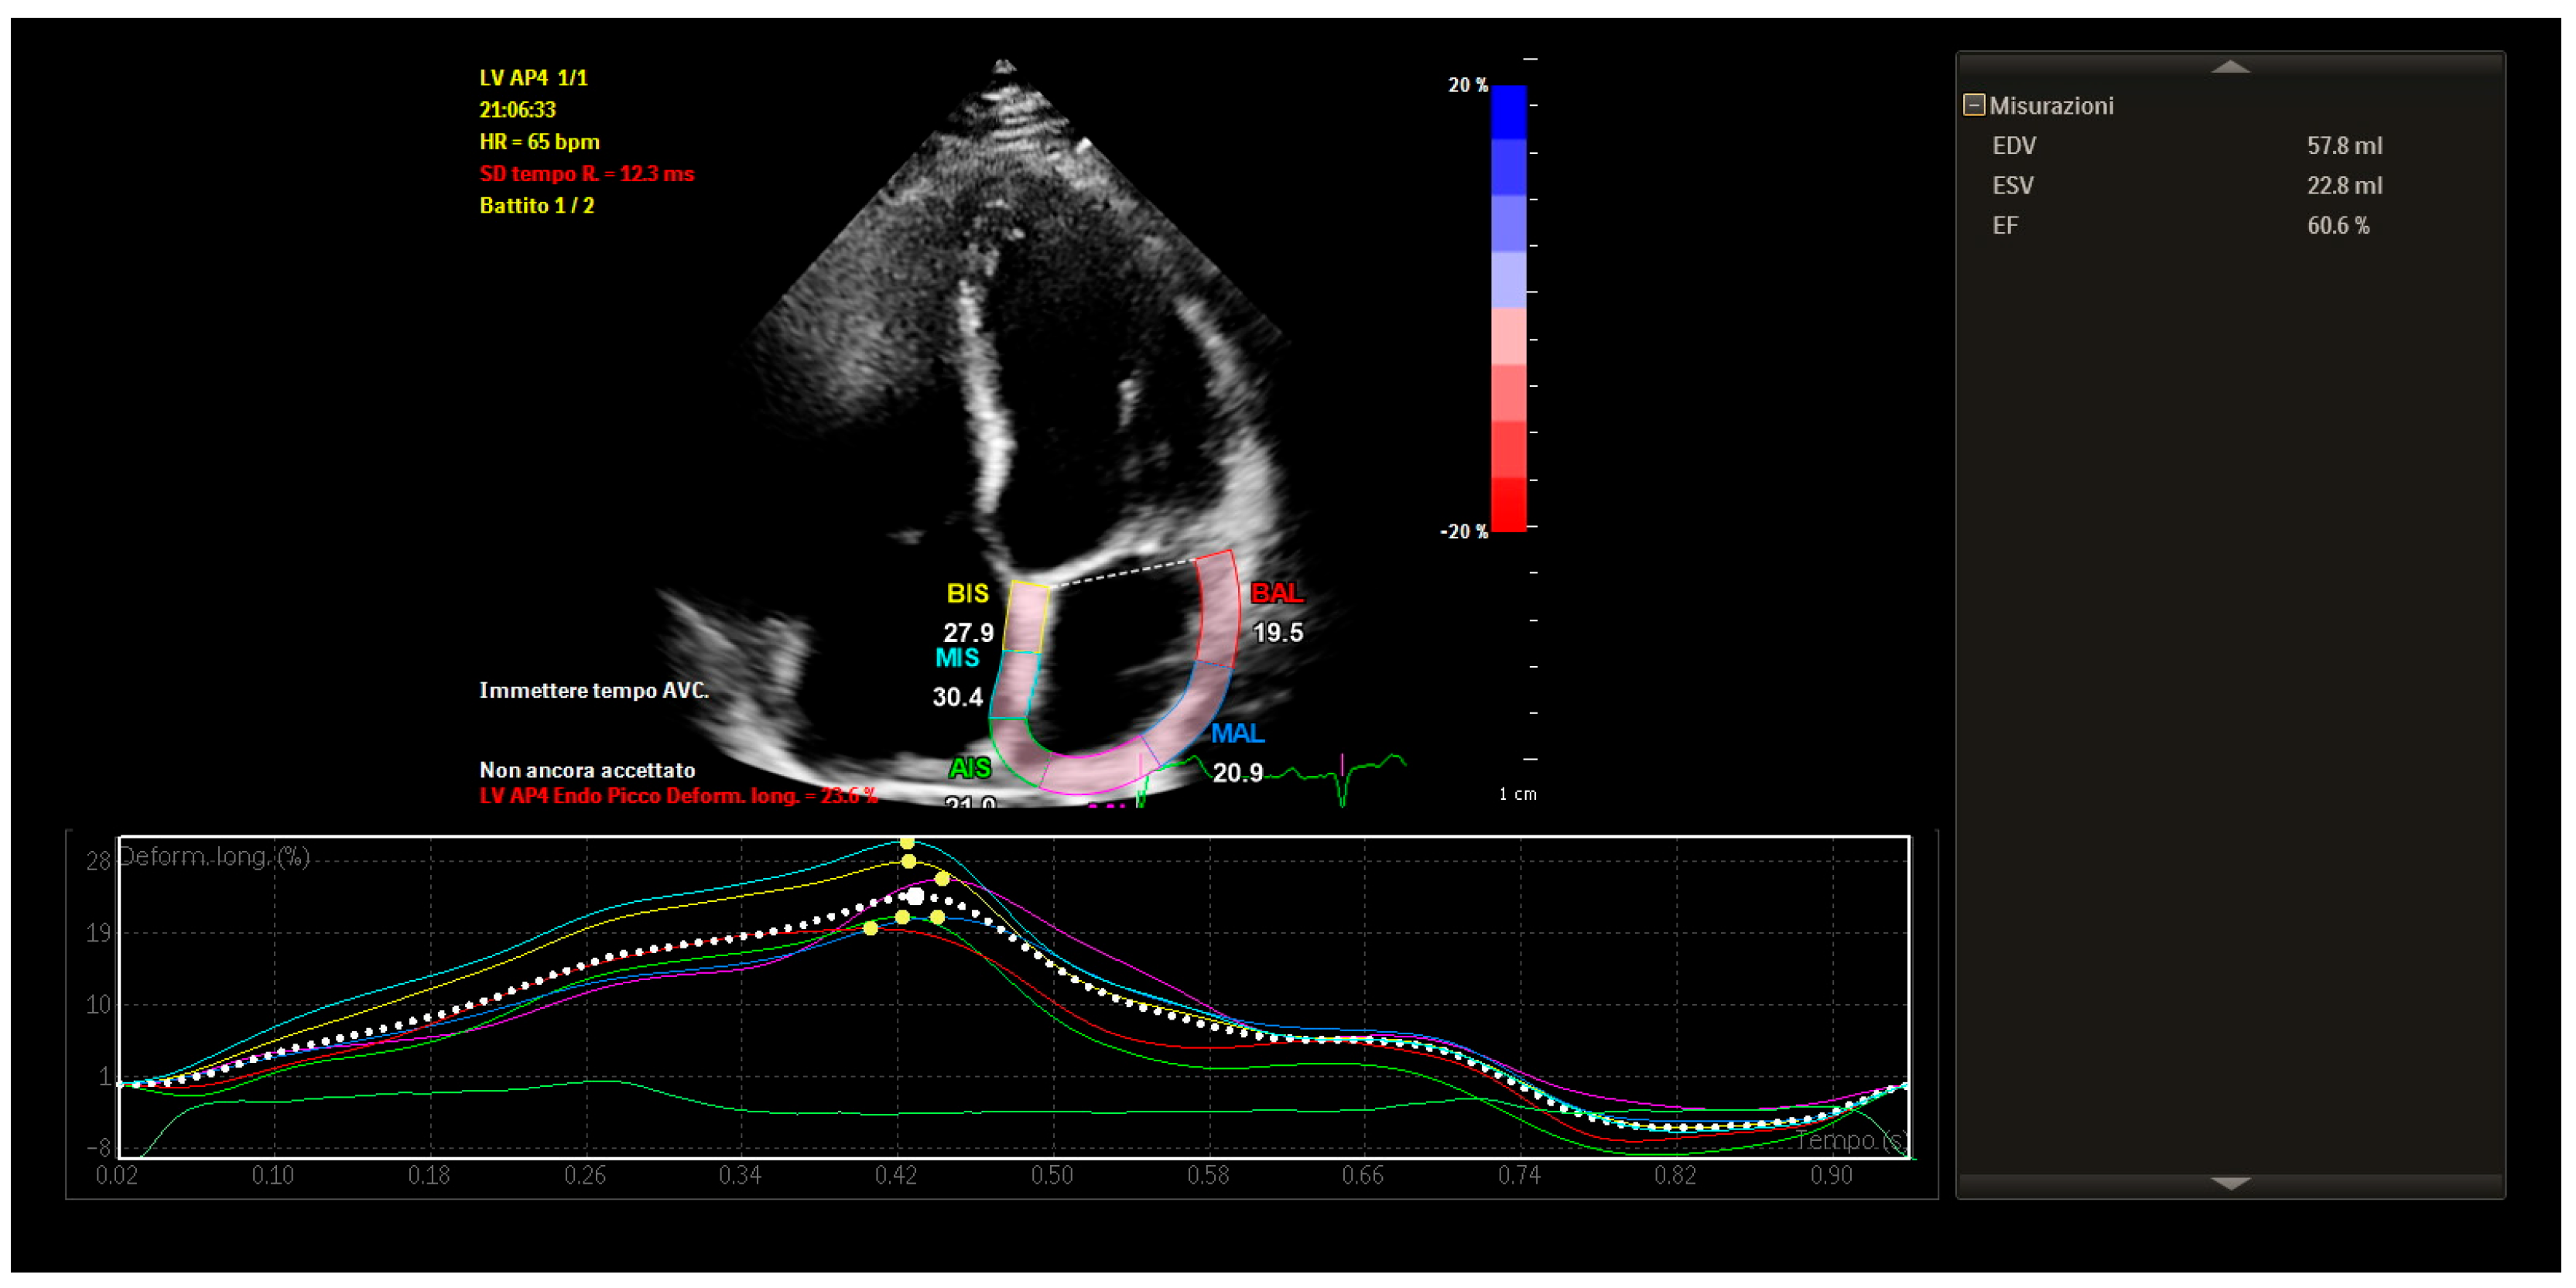

| STE | Speckle-Tracking Echocardiography |